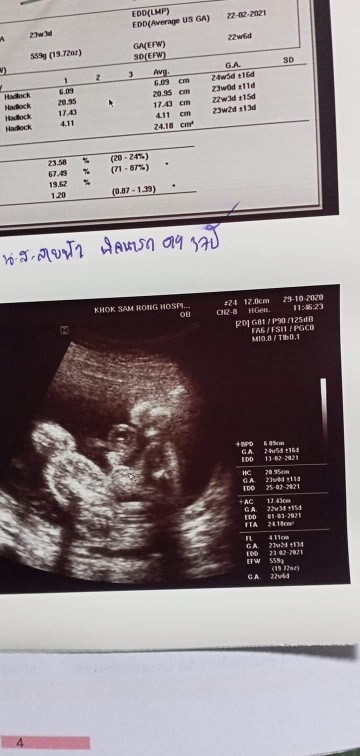

มาอวดภาพอัลตร้าซาวด์กันหน่อยแม่จ๋า 🤰🏻👼🏻 ชาย หรือ หญิง กันนะ?

โพสใต้คอมเมนต์กันได้เลยนะแม่ ♥️ แอดอยากเห็นๆ 7/11/2563